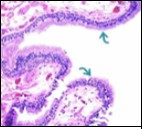

Figure 1.Ciliated cutaneous cyst lined by pseudostratified ciliated columnar epithelium and a supporting fibro-connective tissue stroma 11.

Typically, cutaneous ciliated cyst is a simple cyst which demonstrates a layering of pseudostratified ciliated columnar epithelium recapitulating conventional epithelial lining of the fallopian tube. As the cutaneous ciliated cyst demonstrates a morphological similarity to the fallopian tube lining epithelium, a Mullerian origin is indicated. Gross examination of cutaneous ciliated cyst depicts a solitary, mobile, non-tender, fluctuant, firm or soft to cystic lump with a fibrous wall and abundant amount of circumscribing adipose tissue. Cutaneous ciliated cysts are of a variable dimension. Cut surface usually displays a unilocular cyst impacted with clear, serous fluid, an attenuated smooth, greyish/ white cyst wall incorporated with incomplete septa traversing the cyst 6, 7.

Cutaneous ciliated cyst is layered with a singular layer of ciliated epithelial cells which are chiefly constituted by cuboidal to columnar epithelium, traversed by partially configured fibrous tissue septa with an admixture of randomly dispersed, intraluminal papillary projections akin to those cogitated in the fallopian tube. Superimposed epithelium is inundated with well vascularized, parallel bundles of collagen although smooth muscle is absent 7, 8.

Alternatively, cutaneous ciliated cyst can be lined by non ciliated cuboidal or columnar epithelium with intermingled intercalated, dark or round peg cells. Foci of squamous metaplasia can be occasionally exemplified in the adherent epithelium whereas mucinous cells or apocrine-like features are exceptional 6, 8. Figure 1, Figure 2, Figure 3, Figure 4, Figure 5, Figure 6, Figure 7, Figure 8, Figure 9, Figure 10, Figure 11, Figure 12. 11, 12, 13, 14, 15, 16, 17, 18, 19.